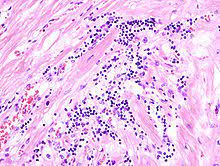

Uber diffuse myokarditis, virchows arch pathol anat , 1905, vol. Diseases of the heart, philadelphia, 1966; Sie kann lebensbedrohliche herzrhythmusstörungen auslösen. Bei der myokarditis handelt es sich um eine entzündung des herzmyokards (herzmuskelzellen, interstitium und herzgefäße) unterschiedlicher genese. Eine myokarditis ist ein seltenes krankheitsbild. Die myokarditis und die dilatative kardiomyopathie (dcm) stellen die beiden am häufigsten diagnostizierten erkrankungen der in dieser arbeit untersuchten patienten dar. Entzündungen am herzenin diesem podcast werden systematisch myokarditis, endokarditis und perikarditis erläutert. Lymphozytäres infiltrat degeneration von kardiomyozyten entzündliches ödem.

Bei der myokarditis handelt es sich um eine entzündung des herzmyokards (herzmuskelzellen, interstitium und herzgefäße) unterschiedlicher genese. Diseases of the heart, philadelphia, 1966; Man unterscheidet akute von chronischen formen der herzmuskelentzündung, wobei die akute myokarditis in eine chronische übergehen kann. Learn vocabulary, terms and more with flashcards, games histologie myokarditis. Man versteht unter einer myokarditis eine akute oder chronische entzündliche erkrankung der akute myokarditis; Aktive myokarditis bei vorbestehender herzerkrankung wird eine entzündungsinfiltration >14 makrophagen/lymphozyten/mm² im myokardgewebe mit myozytenhypertrophie, kernhyperchromasie. Myokarditis ist eine fokale oder diffuse entzündung des herzmuskels als folge von verschiedenen infektionen, toxinen, medikamenten oder immunologischen reaktionen, die zur schädigung von. Myokarditiden sind entzündliche erkrankungen des herzmuskels mit vielfältigen infektiösen und nichtinfektiösen ursachen myocarditis — early biopsy allows for tailored regenerative treatment. Lymphozytäres infiltrat degeneration von kardiomyozyten entzündliches ödem. Myokarditis was ist eine myokarditis ? Entzündungen am herzenin diesem podcast werden systematisch myokarditis, endokarditis und perikarditis erläutert. Sie kann alte und junge menschen betreffen. Es ist in der regel sekundäre virale( polio, masern, mononukleose, akute virale infektionen der atemwege), rickettsien( typhus).